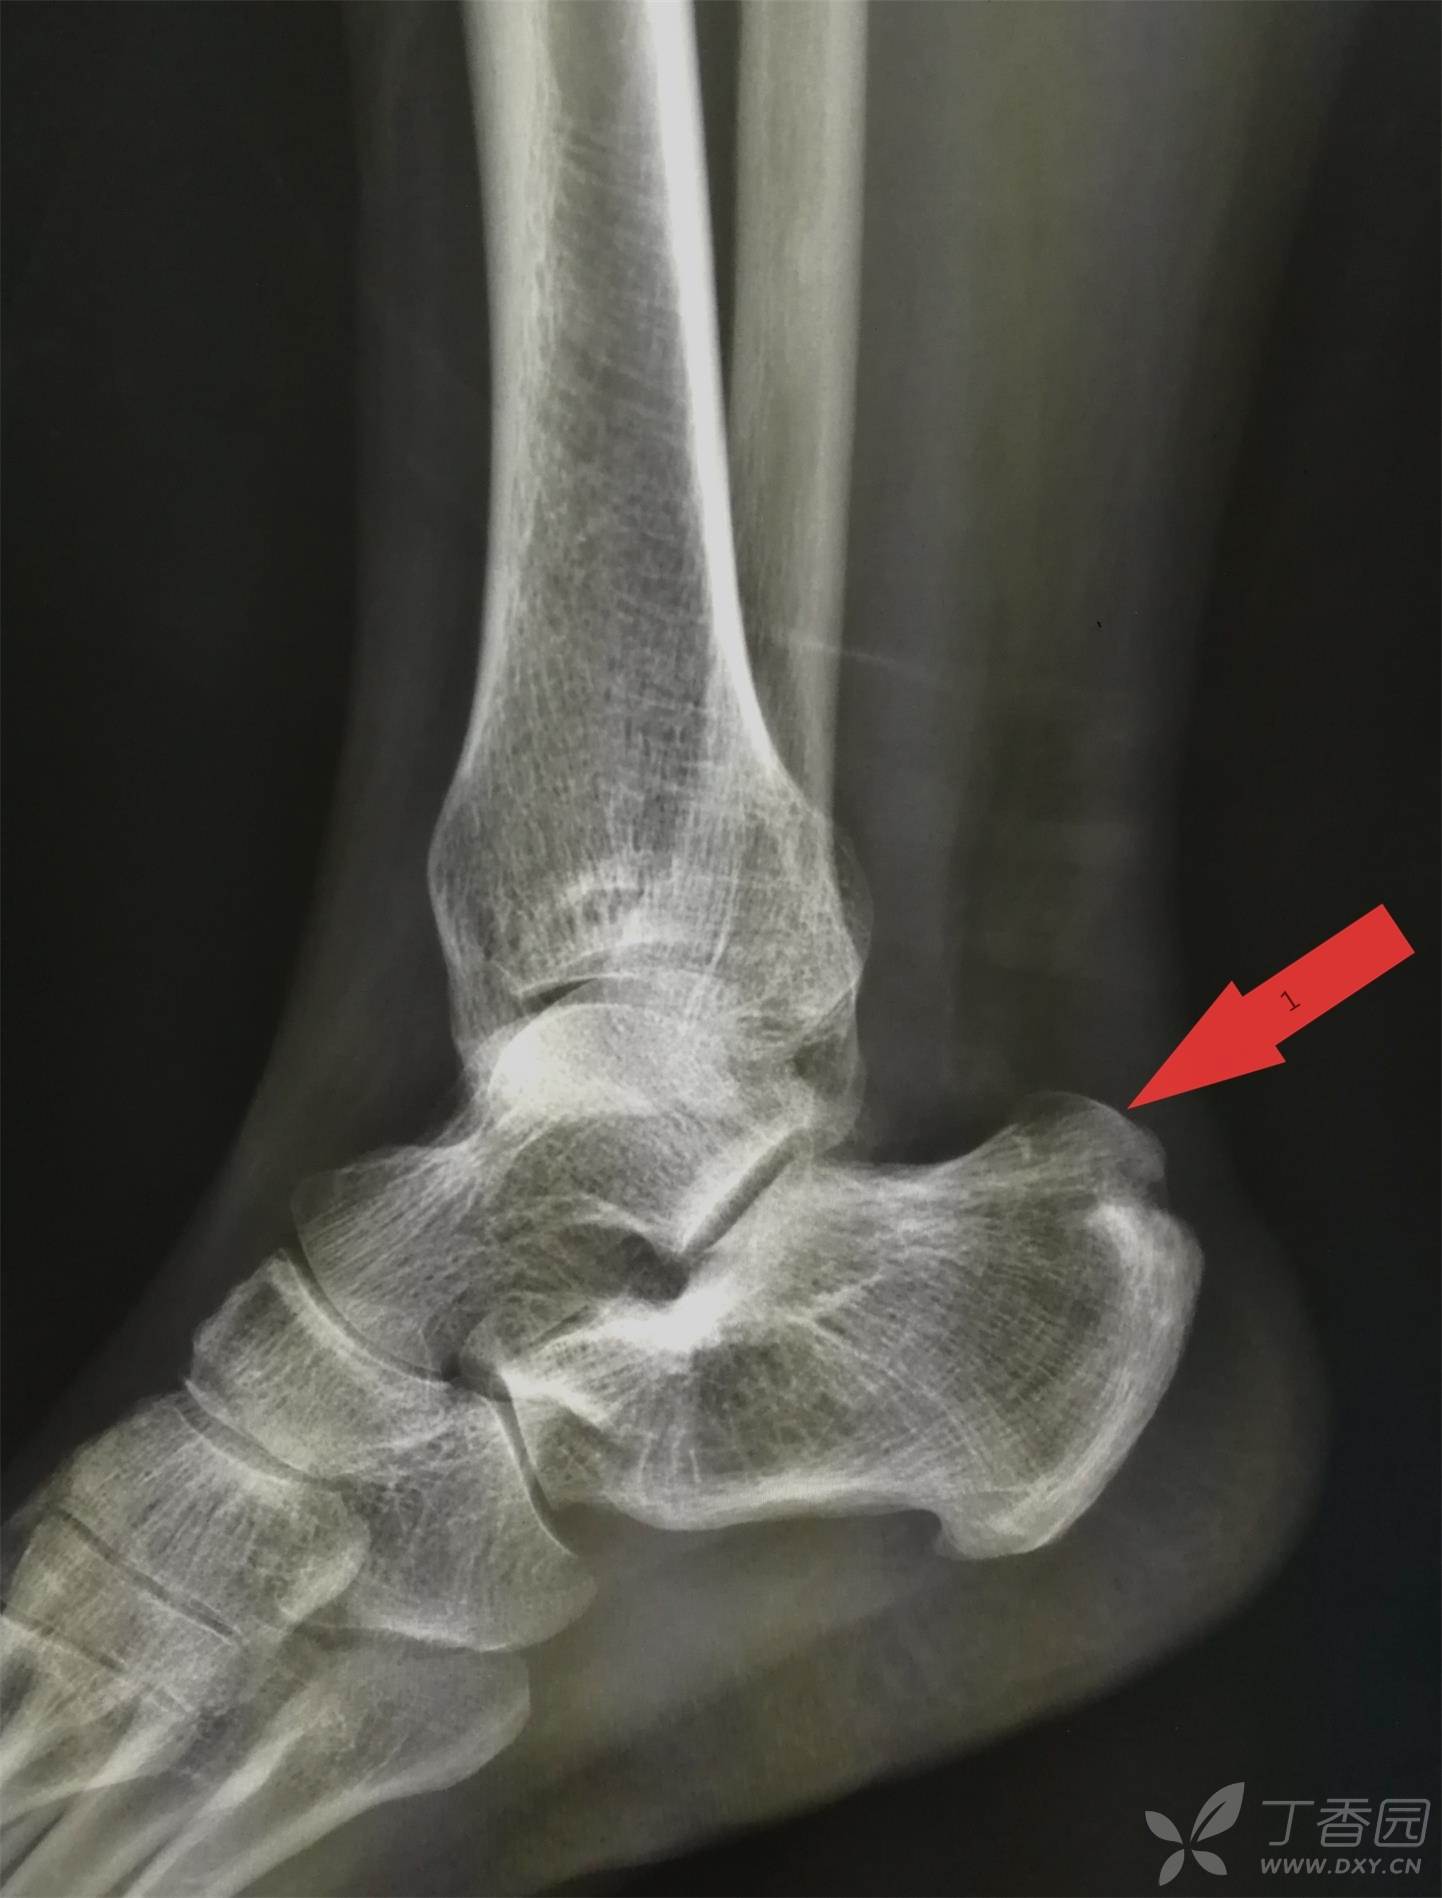

请教一下,这跟骨后上缘突起正常吗?

足跟后方凸起伴疼痛小心跟腱被骨头磨坏